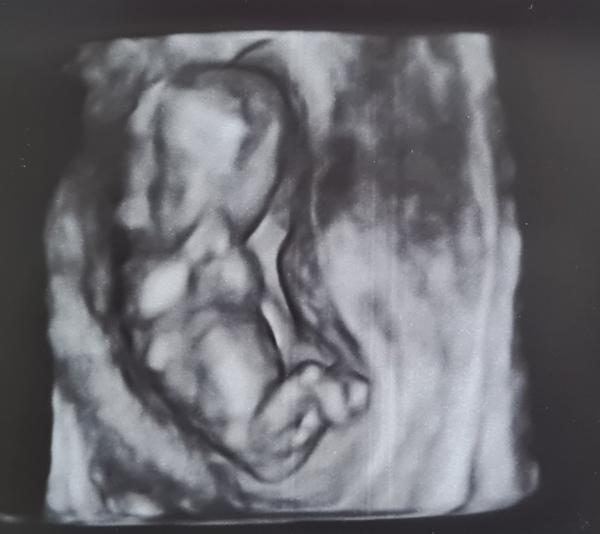

Poznáme pohlaví dítěte ze snímku ultrazvuku?

@lori1097 tak to moc gratuluji, hlavně ať jste oba zdraví😊 no mě to čeká konec června, začátek července, za chvíli to uteče a bude nás také o jednoho člena více😊 já i přítel bychom chtěli chlapečka. Na prvním screeningu nám řekli, že to vypadá na chlapce, ale není si jistá no a od té doby už nevím nic, byla jsem 3x na ultrazvuku a nechtělo se vůbec ukázat 😌 prý se holky spíš nechtějí ukazovat, tak snad. Modlíme se už od začátku za chlapečka😂 Na další ultrazvuk jdu až za měsíc. Jsem tak zvědavá, že si i čtu na internetu babske rady atd, abych se trochu uklidnila😂

@karolina226 Ahoj, podle mě kluk. My měli holčičku a hrbolek byl víc rovně 🙂